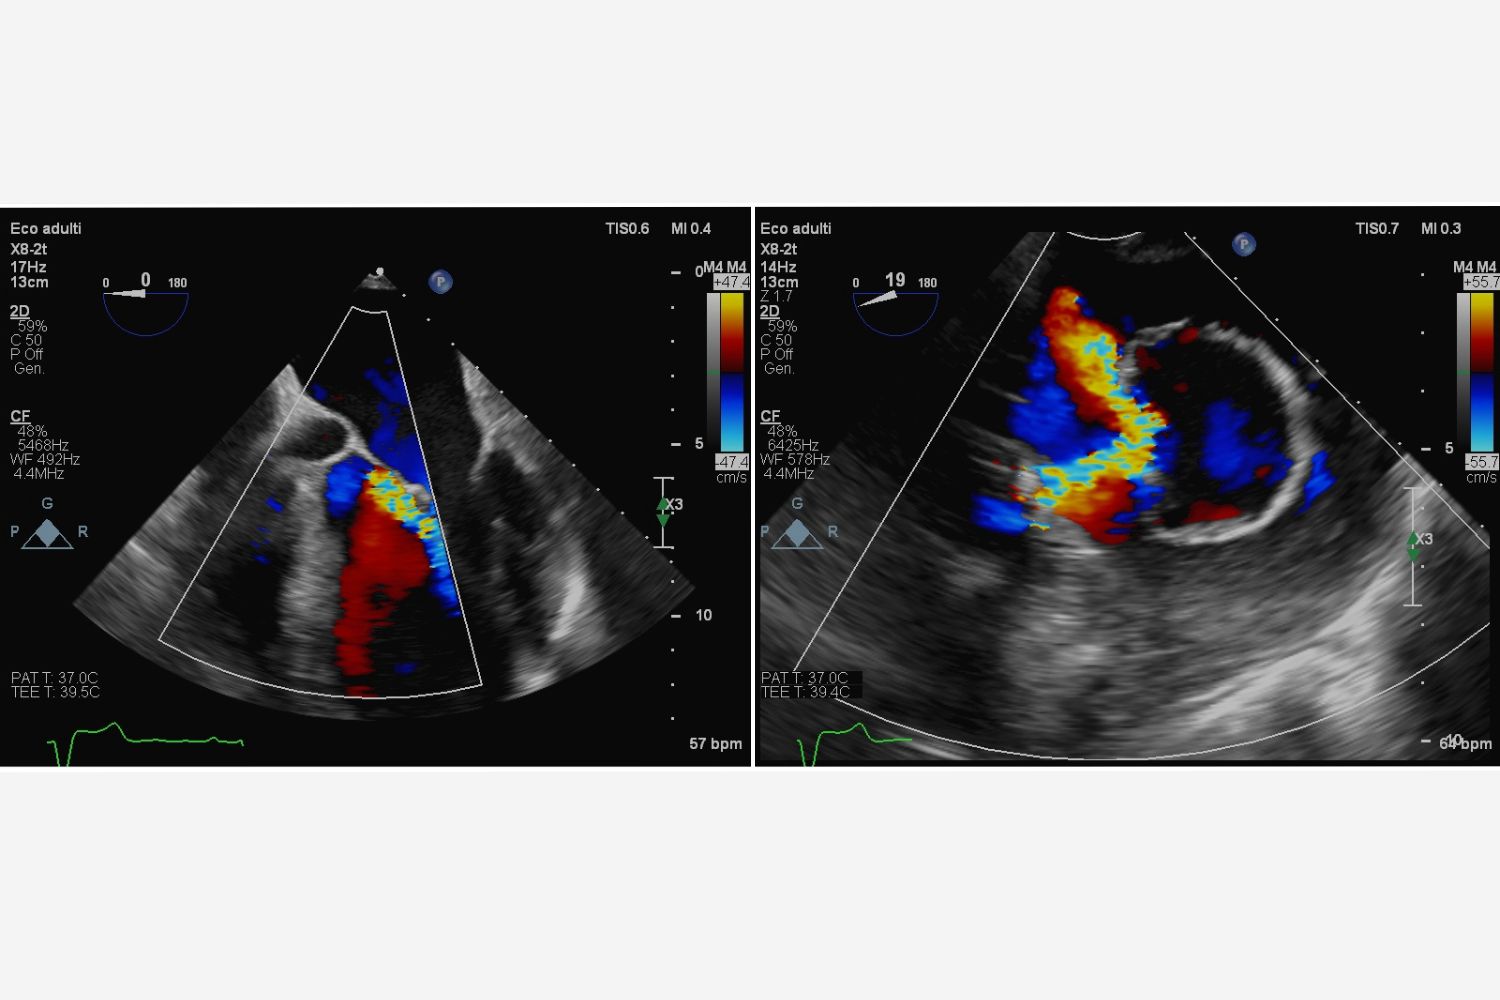

Image of the Week - 5 November 2025